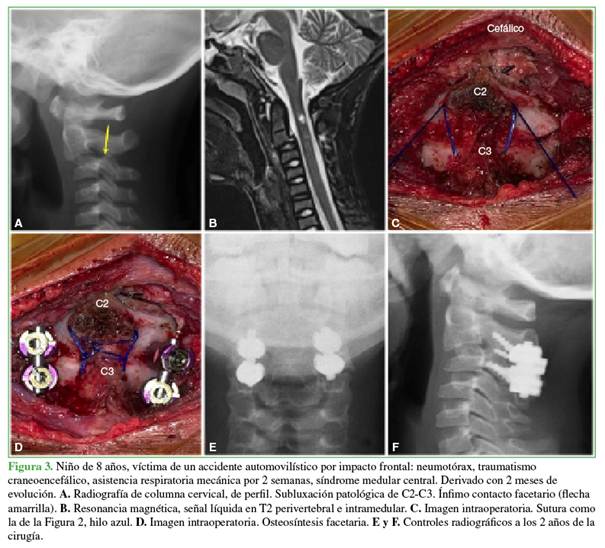

Una vez colocado el campo quirúrgico, se verifica el segmento óseo mediante el intensificador de imágenes y se marca la piel con tinta indeleble. Se emplea un abordaje posterior; luego de incidir la piel y la aponeurosis, se palpan las apófisis espinosas del axis y de C3 a efectos de minimizar todo lo posible el área de exposición; la disección subperióstica se prolonga hasta las apófisis articulares, un detalle importante para prevenir la extensión del área de fusión. Con extrema delicadeza y el uso de pinzas Backhaus se reduce la luxación. Eventualmente puede utilizarse un pequeño disector o elevador perióstico para la movilización facetaria si la reducción es dificultosa. La estabilización primaria se realiza con una sutura compuesta por dos hebras de hilo no absorbible Prolene® 2.0 según dos alternativas: 1) doble cerclaje sublaminar de C2-C3, similar a la técnica de Brooks y Jenkins, pero en un nivel infradyacente (Figura 1)8 y 2) transfixión ósea con una broca de 2,5 mm de diámetro en la unión espinolaminar del axis. Se pasa el hilo a través del túnel tallado y luego se curva por debajo de la apófisis espinosa de C3 sin cruzar la línea media (Figuras 2 y 3).

Ambas técnicas son suficientemente estables para impedir cualquier movilidad accidental durante el resto del procedimiento. A continuación, se realiza la osteosíntesis con tornillos facetarios C2-C3 de 3,5 mm de diámetro con material de adultos o, en una anatomía diminuta, tornillos para minifragmentos de 2,2 mm de diámetro y una placa ad hoc, según la técnica de Magerl. Se procede al control radiográfico final y la adición de un injerto autólogo ilíaco con vancomicina. Se le coloca al paciente un collar blando o de Filadelfia por 8 semanas.

Debido a la falta de material pediátrico específico, se optó por sustituirlo con un material de osteosíntesis para minifragmentos, habitualmente utilizados en cirugías de huesos largos de la mano o del pie, en adultos. Esto se realizó en una niña de 9 meses y en un niño de 4 años. En un paciente de 8 años, se colocó material de osteosíntesis diseñado para adultos. El doble cerclaje sublaminar de C2-C3 lo practicamos en una niña de 9 meses con una lesión lacerante de tejidos blandos que facilitó el pasaje del material de sutura (Figura 1) Sin embargo, a efectos de una estabilización primaria, es suficiente y segura la sutura por transfixión en la espinosa del axis, curvando el hilo debajo de la de C3, seguido del anudado correspondiente. Independientemente del tratamiento, todos los autores informan resultados estables en el tiempo. Por último, McGrory y Klassen comunicaron una extensión de la masa de fusión en el 38% de 42 niños con artrodesis de columna cervical por fracturas y luxaciones.18